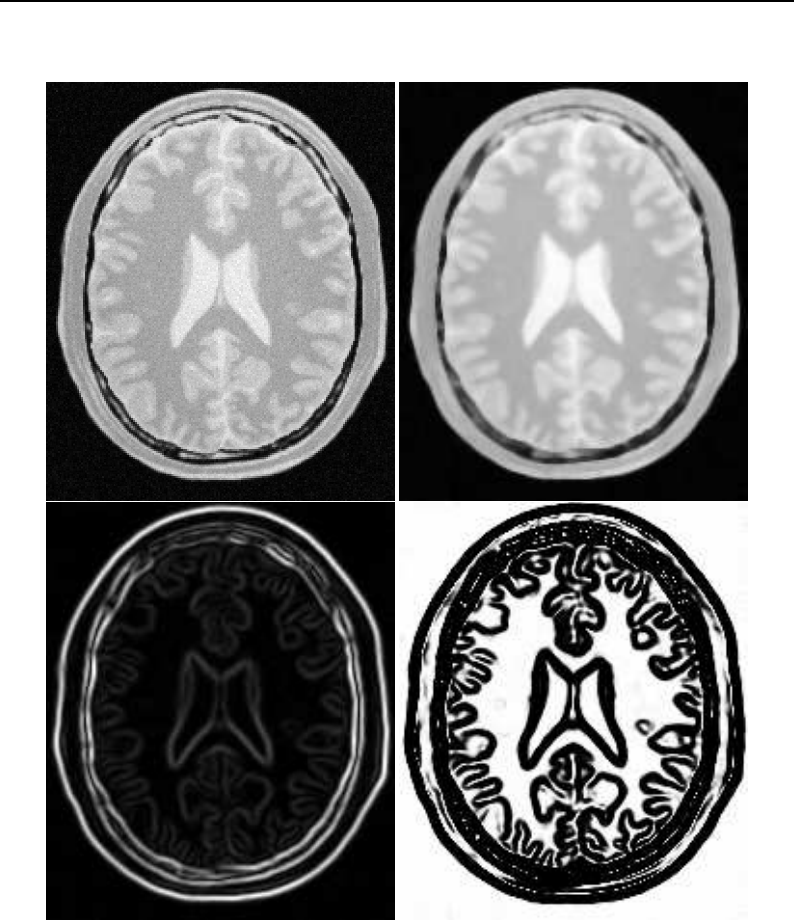

The National Library of Medicine Insight Segmentation and Registration Toolkit, shortened as the

Insight Toolkit (ITK), is an open-source software toolkit for performing registration and segmenta-

tion. Segmentation is the process of identifying and classifying data found in a digitally sampled

representation. Typically the sampled representation is an image acquired from such medical instru-

mentation as CT or MRI scanners. Registration is the task of aligning or developing correspondences

between data. For example, in the medical environment, a CT scan may be aligned with a MRI scan